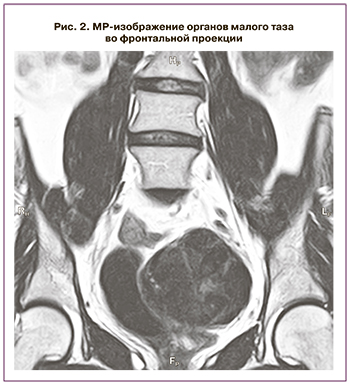

Магнитно-резонансная томография (МРТ) органов малого таза выполнена в трех проекциях в режимах Т1, Т2, DWI с использованием функции подавления сигнала от жировой ткани на фоне артефактов от перистальтики кишечника. Выявлено: матка в типичном месте не визуализируется. В полости малого таза, справа, визуализируется вытянутая мягкотканная структура с четкими неровными контурами. Общие размеры 0,9×6,0 см с наличием на уровне передних отделов узлового образования размерами 1,4×1,9 см. Схожее по МР-характеристикам мягкотканное включение слева, с наличием двух узлов, размерами 6,9×8,6×6,5 см и 2,0×1,6×2,7 см. Яичники расположены выше описанных мягкотканных структур, размерами: справа – 1,2×1,9×2,0 см, слева – 1,3×2,1×1,2 см. Капсула яичников не утолщена, строма неоднородного пониженного МР-сигнала, фолликулы не определяются (рис. 1, 2).